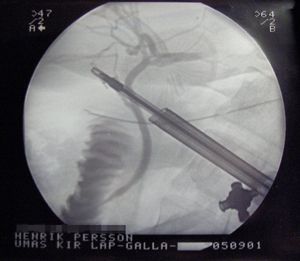

현재는 복부에 5mm에서 10mm의 작은 구멍을 3~4군데 뚫어 복강경으로 환자의 체내를 확인하면서 시행하는 복강경 담낭 절제술이 주류를 이루고 있다. 개복 수술에 비해 일상생활로의 복귀가 빠르고, 환자의 부담도 적다는 장점이 있다. 담낭염의 진행 정도나 기타 병상에 따라 복강경 수술이 불가능한 상황도 있다. 사전 검사에서 복강경 담낭 절제술을 시행할 수 있다고 진단받더라도 수술을 시작하고 처음 밝혀지는 병상이 있기 때문에 5%의 확률로 수술 중 개복 수술로 변경될 가능성이 있다.

5. 2. 담낭 절제술

대부분의 급성 쓸개염 환자에게 선택되는 치료법은 복강경 담낭 절제술을 통한 담낭의 외과적 제거이다.[32] 복강경 담낭 절제술은 복부 전체의 여러 지점에 위치한 몇 개의 작은 절개를 사용하여 수행된다. 여러 연구에서 개복 담낭 절제술(늑골 아래 오른쪽 상복부에 큰 절개를 사용하는 경우)에 비해 복강경 담낭 절제술의 우수성이 입증되었다. 복강경 수술을 받는 사람들은 수술 후 절개 부위 통증이 적고, 장기적인 합병증과 수술 후 장애가 적다고 보고한다.[33][34] 또한, 복강경 수술은 수술 부위 감염률이 낮다.[35]

증상으로 의사를 찾은 지 7일 이내에 조기 복강경 담낭 절제술을 받는 경우, 지연된 치료(6주 이상)에 비해 입원 기간이 짧고 응급 처치를 받아야 할 위험이 감소할 수 있다.[37] 조기 담낭 절제술의 경우 개복 수술로의 전환의 가장 흔한 이유는 칼로 삼각을 가리는 염증 때문이다. 지연된 수술의 경우 가장 흔한 이유는 섬유성 유착이었다.[37]

현재는 복부에 5mm에서 10mm의 작은 구멍을 3~4군데 뚫어 복강경으로 환자의 체내를 확인하면서 시행하는 복강경 담낭 절제술이 주류를 이루고 있다. 개복 수술에 비해 일상생활로의 복귀가 빠르고, 환자의 부담도 적다는 장점이 있다.

최근에는 복강경을 이용한 담낭 절제술이 주류를 이루고 있다.[45] 복강경 담낭 절제술은 복부에 5mm에서 10mm의 작은 구멍을 3~4군데 뚫어 시행하며, 개복 수술에 비해 회복이 빠르고 환자의 부담이 적다는 장점이 있다. 그러나 담낭염 진행 정도나 기타 병상에 따라 복강경 수술이 불가능할 수 있으며, 수술 중 개복 수술로 변경될 가능성도 5% 정도 존재한다.